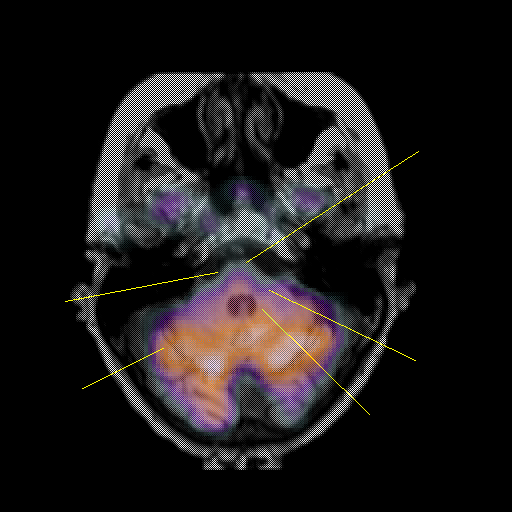

overlay: Slice 13

Slice 13

Pointers

Labeled